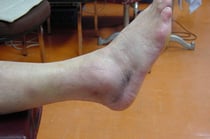

○ 足関節捻挫

ご紹介する症例は、たいへん腫れていますがすべて骨折を伴わない捻挫です。

捻挫とは関節が思わぬ外力により本来制限されるべき可動範囲を超え軟部組織を壊してしまったことを言います。

○足関節捻挫 関節不安定症

大学生 女子

小学生の頃からバスケットボールをしています。何度も捻挫やケガの既往があり今回もプレー中に強く捻ってしまいました。整形外科で診察を受けたところ剥離骨折が確認されギプス固定を一ヶ月ほどすることになっていました。

本人は3週間後の学生最後の試合に参加したい希望があり当院に相談に来られました。

触診したところ剥離骨折しやすいところには骨折特有の圧痛が認められなかったので、陳旧性の骨折(過去のけがの痕)ではないかと、再度信頼できる整形外科医を紹介しました。 検査の結果やはり新しい骨折ではありませんでした。もちろん靱帯 腱は損傷しているのでテーピング等の固定は必要になりますが、ギプスよりは楽になります。

当初は両手に松葉杖でタクシーで学校に通っていました。

現在、捻挫の治療をして最後の試合に参加できるように毎日治療中です。

本当はやってはいけませんが、テーピングでちょっと参加してもらう予定です。